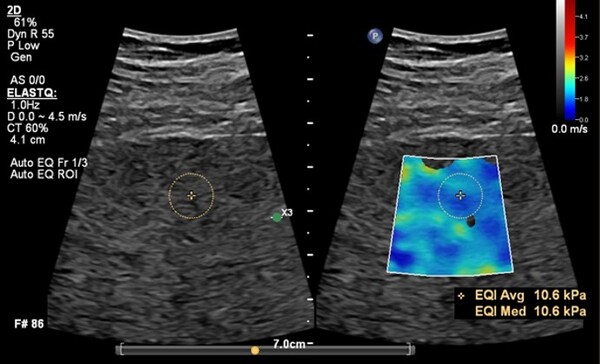

새로운 버전의 에픽 엘리트에는 워크플로우를 향상하는 간섬유화 검사 기능인 ‘오토 엘라스트큐(Auto ElastQ)’를 새롭게 탑재했다. 전단파 탄성 초음파(Shear Wave Elastography,SWE) 데이터를 자동으로 분석하고 최적의 측정 프레임과 검사 관심 영역(ROI, Region of Interest)을 설정하는 기능으로 검사 효율성과 진단 정확도를 향상한다. 기존에는 의료진이 수동으로 프레임과 ROI를 지정해야 했으나, 이제는 시스템이 자동으로 최적의 측정 위치를 설정하여 더욱 빠르고 정밀한 검사가 가능하다. 이를 통해 검사 시간이 기존 대비 60% 단축되고, 키 스트로크(조작 횟수)가 29% 감소해 의료진의 업무 부담을 줄이는 데 기여한다.